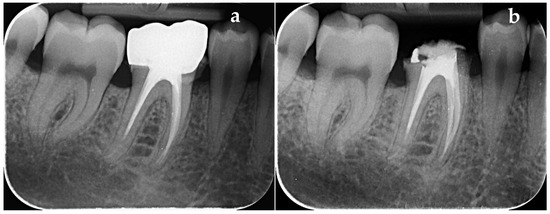

3.2. Paraclinical Evaluation

3.2.1. Evaluation of the PAI Score on Group with Dehydrated Plant Extract

3.2.2. Evaluation of the PAI Score on Group with Calcium Hydroxide